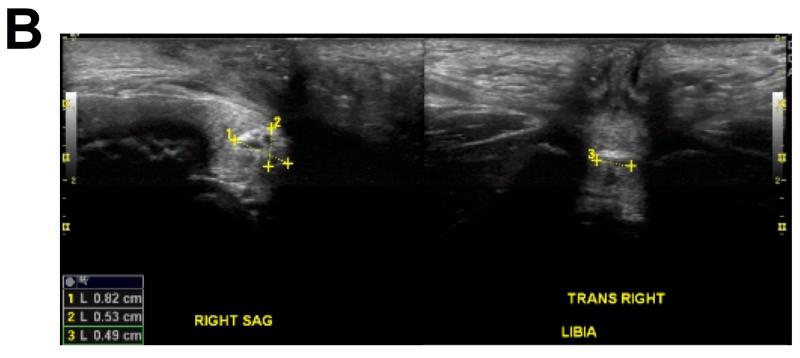

Vaginal discharge in prepubescent girls is not an uncommon problem in pediatric outpatient practice. Among its various etiologies, foreign body lodgement is quite frequent in this age group. Diagnosis is sometimes forthcoming after history and physical exam, and the removal of the foreign object is followed by a prompt resolution of symptoms. However, in rare circumstances, an intravaginal foreign body may mimic other pathologies, including infections and neoplasms, as well as raising suspicion for child abuse. In such cases, diagnosis may remain unclear even after laboratory tests and imaging studies. We describe a seven-year-old girl with vaginal discharge, who needed inpatient admission, multiple imaging studies and, finally, exploration under anesthesia to confirm the diagnosis of foreign body (fecal mass) lodgement and its removal. This is a very rare case where the lodgement of an intravaginal fecal mass in a child led to such protracted symptoms requiring extensive diagnostic and therapeutic maneuvers, in the absence of any structural abnormality of the urogenital tract.

青春期前女童的阴道分泌物在儿科门诊实践中并非罕见问题。在其各种病因中,异物存留在这个年龄组相当常见。有时通过病史和体格检查即可做出诊断,取出异物后症状会迅速缓解。然而,在罕见情况下,阴道内异物可能会模仿其他病理情况,包括感染和肿瘤,同时也会引发对虐待儿童的怀疑。在这种情况下,即使经过实验室检查和影像学研究,诊断仍可能不明确。我们描述了一名七岁有阴道分泌物的女童,她需要住院,进行多项影像学检查,最后在麻醉下探查以确诊异物(粪块)存留并将其取出。这是一个非常罕见的病例,儿童阴道内粪块存留导致了如此迁延的症状,需要进行广泛的诊断和治疗操作,而泌尿生殖道并无任何结构异常。